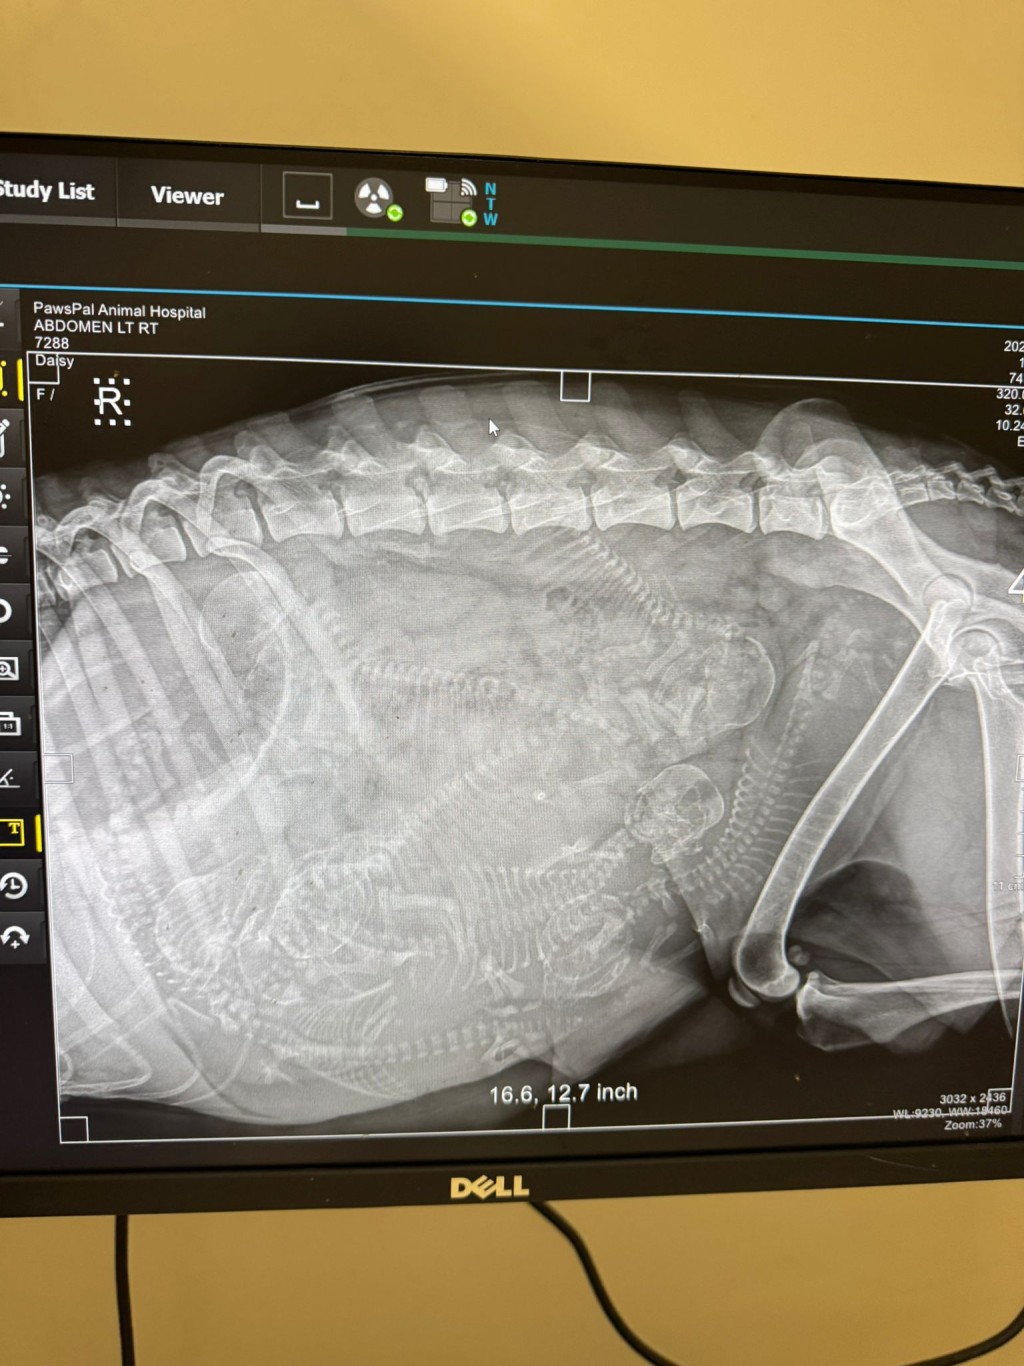

獸醫為牠進行檢查,驗血發現牠有貧血,而且已經懷孕,從X光中可以清楚見到有6個已經發育成形的寶寶,估計寶寶在這個星期內便會出生。

Angela媽媽說當獸醫照到狗狗肚內有7個BB時,她的情是又驚又喜,驚的是那麼瘦弱的狗狗要做媽媽,喜的是BB們仍有心跳,正努力求助。Angela説:「我𪊴幸可以及時救到她出來。」